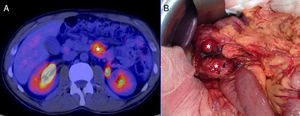

We present the case of a 40-year-old man with neurofibromatosis type 1 undergoing treatment for anaemia of 2 months evolution, and in the last full blood count he presented haemoglobin of 6mg/dl. The patient was asymptomatic, with the exception of dark faeces. The upper gastrointestinal tract endoscopy (UGIE) of the third part of the duodenum showed a 3–4cm ulcerated tumour with a stable adhered clot. No biopsies were taken due to the risk of bleeding. A second UGIE was performed 4 days later, with a pathological anatomy outcome of duodenal ulcer with regenerative changes on the borders. After the abdominal CT scan, which identified a lesion in the third part of the duodenum, without being able to reach a conclusion about the nature thereof, a PET/CT scan was performed (Fig. 1A), diagnosing him with a 4cm poorly-delimited hypermetabolic duodenal lesion, suggestive of a neoplastic lesion, with no other lesions (Fig. 1B). A surgical intervention was carried out, finding, via visual inspection and palpation, two lesions smaller than 1cm of neoplastic appearance in the proximal jejunum together with two others (1×1 and 4×3cm) on the non-pancreatic side of the third part of the duodenum, with the latter probably causing the symptoms of gastrointestinal bleeding. No other lesions were found in the intestine or stomach. Given the lack of a histological perioperative diagnosis of the lesion and with this being important for the surgical approach to follow, an intraoperative biopsy was performed, reporting a GIST. Since the lesion was located in the third part of the duodenum, it had to be ensured that the opening of the bile duct—located in the second part of the duodenum, next to the resection area—was not injured, therefore a cholecystectomy was performed along with identification of the ampulla of Vater by means of bile duct canalisation with a Fogarty probe via the cystic duct. After identification, a duodenectomy of the third and fourth parts of the duodenum was performed, including the lesions in the contiguous proximal jejunum (Fig. 2A). The intestinal tract was reconstructed via duodenal-jejunal termino-terminal anastomosis and placement of a TachoSil® patch (Fig. 2B). The post-operative period proceeded without complications, with discharge after 8 days. The pathological anatomy report showed the presence of a multiple stromal tumour (4 lesions) of low degree of malignancy (<4cm and <5 mitotic figures per 50HPF) and positive c-kit, receiving no adjuvant oncological treatment. Two months after the surgical intervention, a capsule endoscopy was performed, ruling out the existence of other lesions throughout the digestive tract that may not have been detected intra-operatively. The patient was asymptomatic and had no relapses at 15 months.

A diagnosis of GIST is based on the UGIE and an abdominal CT or MRI scan, with a PET/CT scan being helpful in the event of any diagnostic doubt, as occurred in the described case.3,5,7,10